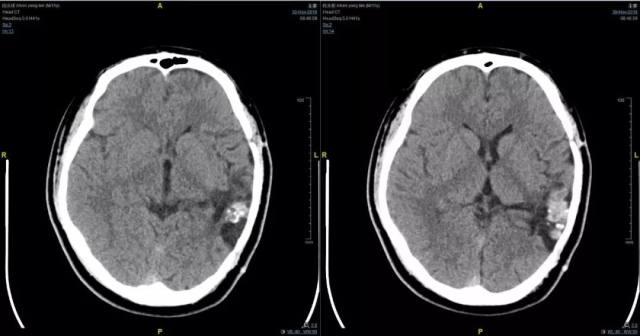

2、术前影像资料

图 1 术前 CT:左颞顶枕术后;局部混杂密度影,考虑出血伴钙化,请结合临床。